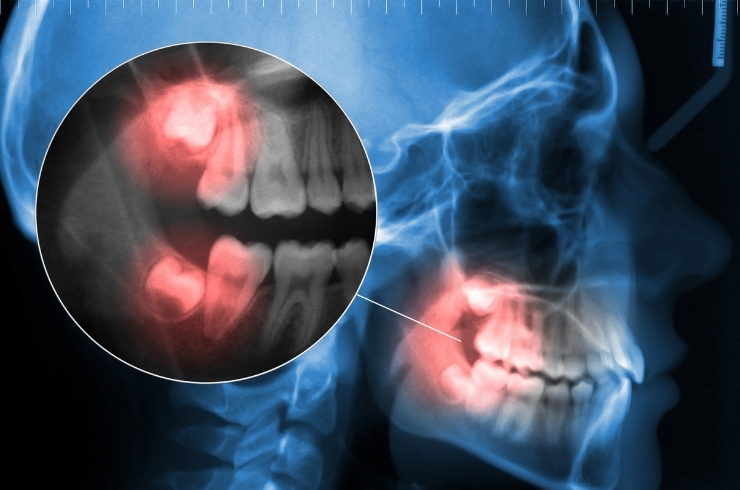

Wisdom Tooth Extraction

Safe removal of problematic wisdom teeth to prevent pain, infection, misalignment, and other complications while ensuring smooth healing and comfort.